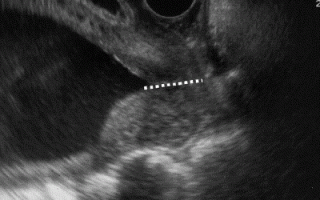

Данные при УЗИ шейки матки

Расшифровка данных, норма показателей

Расшифровка полученных данных проводится только лечащим акушером- гинекологом. Врач-узист только описывает отклонения. После получения результатов на руки, у пациентки возникает масса вопросов, из-за того, что выявляется масса непонятных значений. Чтобы понять проведенную диагностику рекомендуется знать показатели, которые являются нормальными.

Обследование УЗИ является комплексным, поэтому правильная расшифровка очень важна для дальнейшего определения диагноза. Выявляются следующего типа обследования:

При диагностике шейки матки у пациентки любого возраста нормальными показателями являются следующие параметры:

1. Длина шейки должна быть в пределах 3,5-4,5 см.;

2. Маточный зев – нормальное раскрытие: не больше 5 мм;

3. В цервикальном канале должна быть свободная проходимость: отсутствуют ненормальные эхо-сигналы, отсутствие полипов и миоматозного узла субмукозного типа;

4. Структура цервикального канала и эпителия внутреннего органа – четкая, без изменений и патологий;

5. Отсутствие признаков «минус-ткань» или «плюс-ткань», которое выявляется при развитии новообразований злокачественного типа.

Дополнительно учитывается локализация матки относительно других внутренних органов. Дисплазию эхография не выявляет, при этом фиксирует возникшие рубцы от хирургического вмешательства.